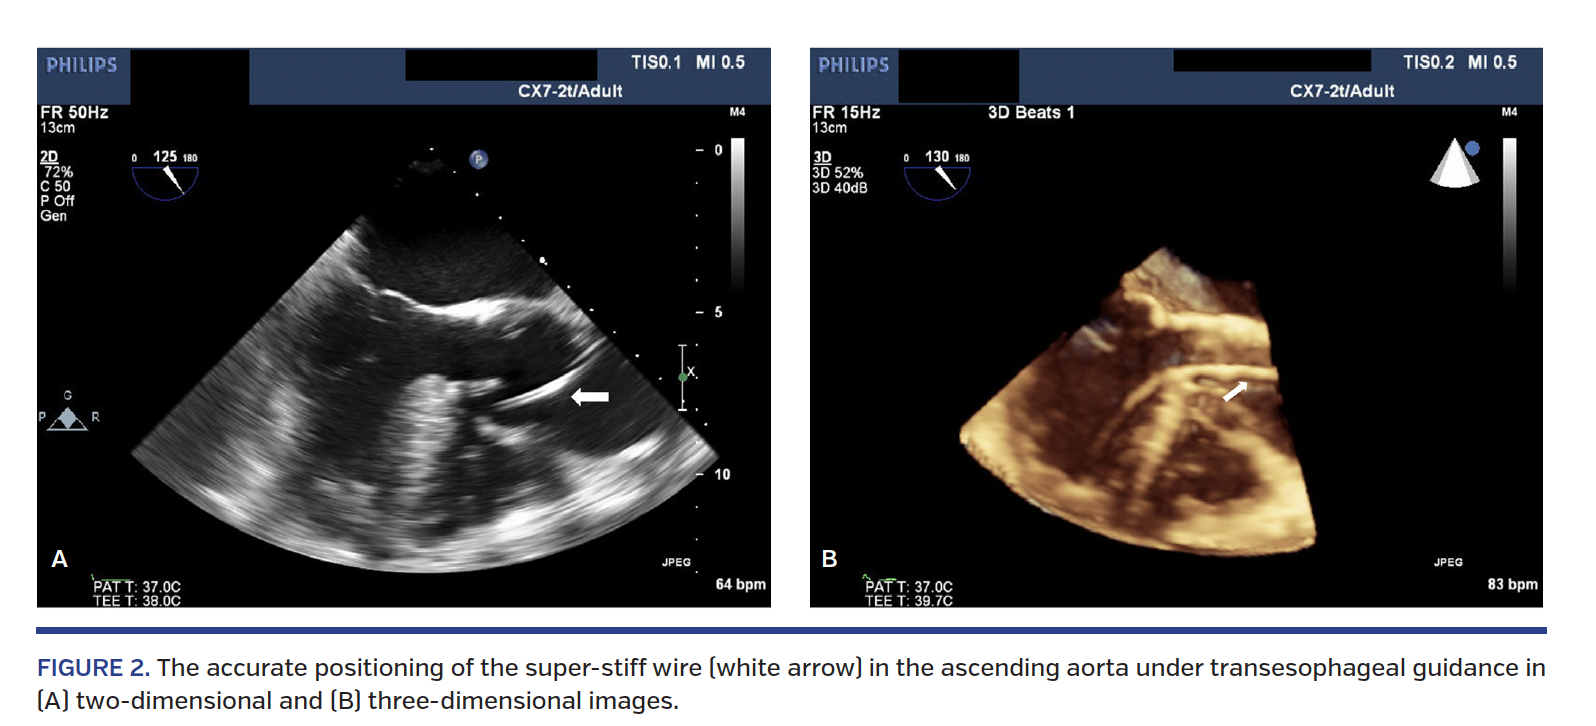

The heart team decided on surgical aortic valve replacement. However, surgery was abandoned due to extensive adhesions between the sternum and the aorta (hostile mediastinum). We therefore elected to perform a transapical transcatheter aortic valve replacement (TAVR). CT imaging showed minimal calcification in the aortic valve leaflets and measurements suggested that a 29 mm Edwards S3 valve (Edwards Lifesciences) would be suitable. Careful antegrade valve crossing was performed using only a standard 0.038˝ wire and a 5 Fr Pigtail catheter under transesophageal echocardiographic (TEE) guidance (Figures 2A and 2B). Following true lumen confirmation, an exchange was made with a super-stiff wire and the valve was successfully deployed slowly at 50/50 position across the native annulus (Video 1) with only mild residual paravalvular aortic regurgitation by aortogram (Video 2) and TEE (Video 3).

To the best of our knowledge, this is the first reported case of TAVR in a patient with severe native aortic valve regurgitation in the presence of aortic dissection. In our case, the challenge was not only the deployment of a balloon-expandable valve, but also the presence of the aortic dissection flap, which could have been made worse by the wire manipulation. A transapical approach was chosen to avoid any extension of the dissection if a transfemoral or trans-subclavian route were used. The only available transapical valves in our lab are Edwards S3 valves. The CT scan measurement showed that a 29 mm valve (oversized by 20%) would offer more stability to the valve against the aortic annulus to prevent its dislocation. The use of intraprocedure two- and three-dimensional TEE enabled us to confidently identify the exact location of the dissection flap and guide the course of the pigtail catheter, allowing for safe exchange with the super-stiff wire.